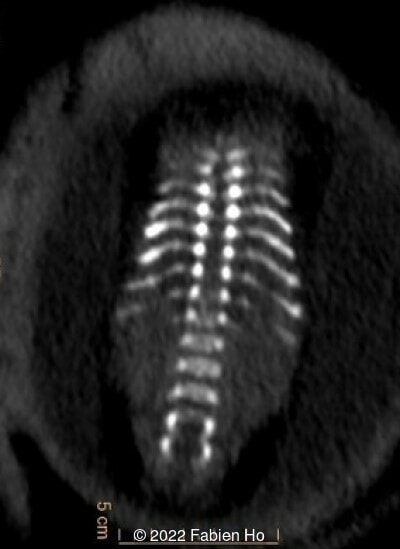

A CT scan was subsequently performed at 32 weeks gestation

The prenatal CT scan showed:

- Low bone density of skull and lower limbs

- Moderately narrowed and bell-shaped thorax

- Numerous bone calluses of the posterior arcs of the ribs

- Normal bone density of the spine

- No platyspondyly

- Normal pelvis without iliac spine or other anomaly

- Very short long bones with curved femurs, tibias and fibulas. The curvature of the long bones reaches a 90° angle concerning for fracture. Upper limbs are moderately curved without fracture.